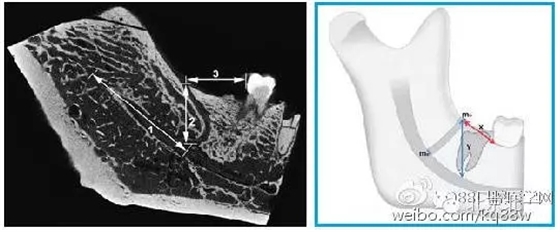

下頜磨牙后管(retromolar canal,RMC)通常起自與第三磨牙后方的下頜管,并向上走行在磨牙后三角區(qū)開口于磨牙后孔(retromolar foramen,RM

640.webp (1).jpg

圖二 磨牙后孔位置圖示(紅色箭頭):A.磨牙后孔位于磨牙后區(qū)正中矢狀線舌側(cè);

B.磨牙后孔位于磨牙后區(qū)正中矢狀線上;C.磨牙后孔位于磨牙后區(qū)正中矢狀線頰側(cè)。

圖四 磨牙后管的線性測(cè)量

1.從下頜孔到下頜磨牙后管分支起點(diǎn)的距離;2.下頜磨牙后管的垂直高度(X);3.從下頜后孔到第二或第三磨牙遠(yuǎn)中的水平距離(Y)。